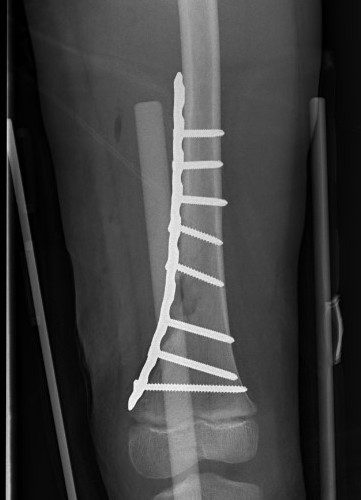

Salter Harris Type II with large Thurston Holland fragement

Distal Femur Salter Harris 2Distal Femur Salter Harris 2

Technique

AO foundation screw fixation Salter Harris Type II

Reduction

- attempt closed

- may be periosteum blocked on tension / medial side

Medial subvastus approach to knee

- identify Thurston-Holland fragment

- physeal sparing metaphyseal screws

Distal Femur SH2 ORIFDistal Femur SH2 ORIFDistal Femur SH2 Lateral